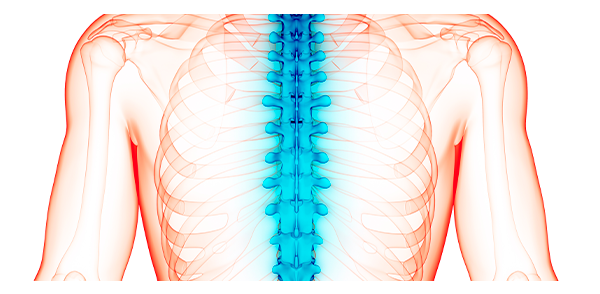

O que é um procedimento minimamente invasivo da coluna?

Os procedimentos minimamente invasivas da coluna são o que há de mais sofisticado em técnicas cirúrgicas de tratamento de coluna. É por meio dessa técnica que os procedimentos têm se tornado cada vez mais satisfatórios, já que os possíveis efeitos colaterais de uma cirurgia da coluna convencional são mínimos.

Para quem é indicado o procedimento minimamente invasivo da coluna?

O procedimento minimamente invasivo é indicado, para o tratamento de dor nas costas (lombalgia), dor cervical (pescoço), dor ciática, hérnia de disco lombar ou cervical, doença degenerativo discal lombar e cervical, fratura por osteoporose